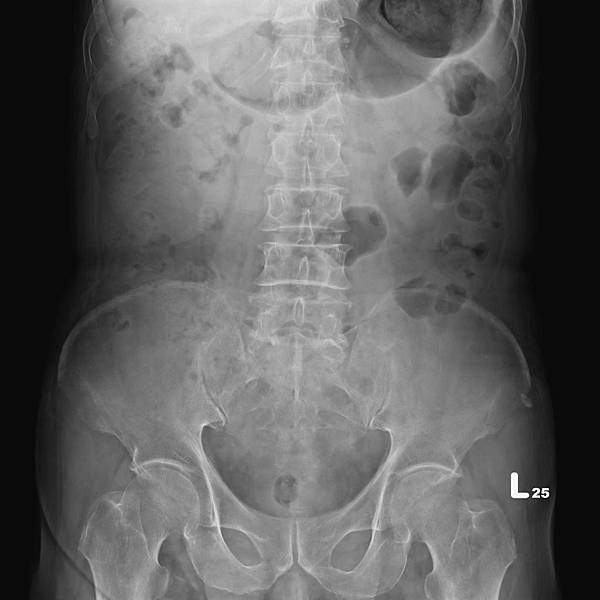

KUB看不出她的病有多嚴重:

WBC 13600/ul, Seg 93.4%

CRP 48.7 mg/dL

看到這些抽血數值,大家都會猜急性闌尾炎。